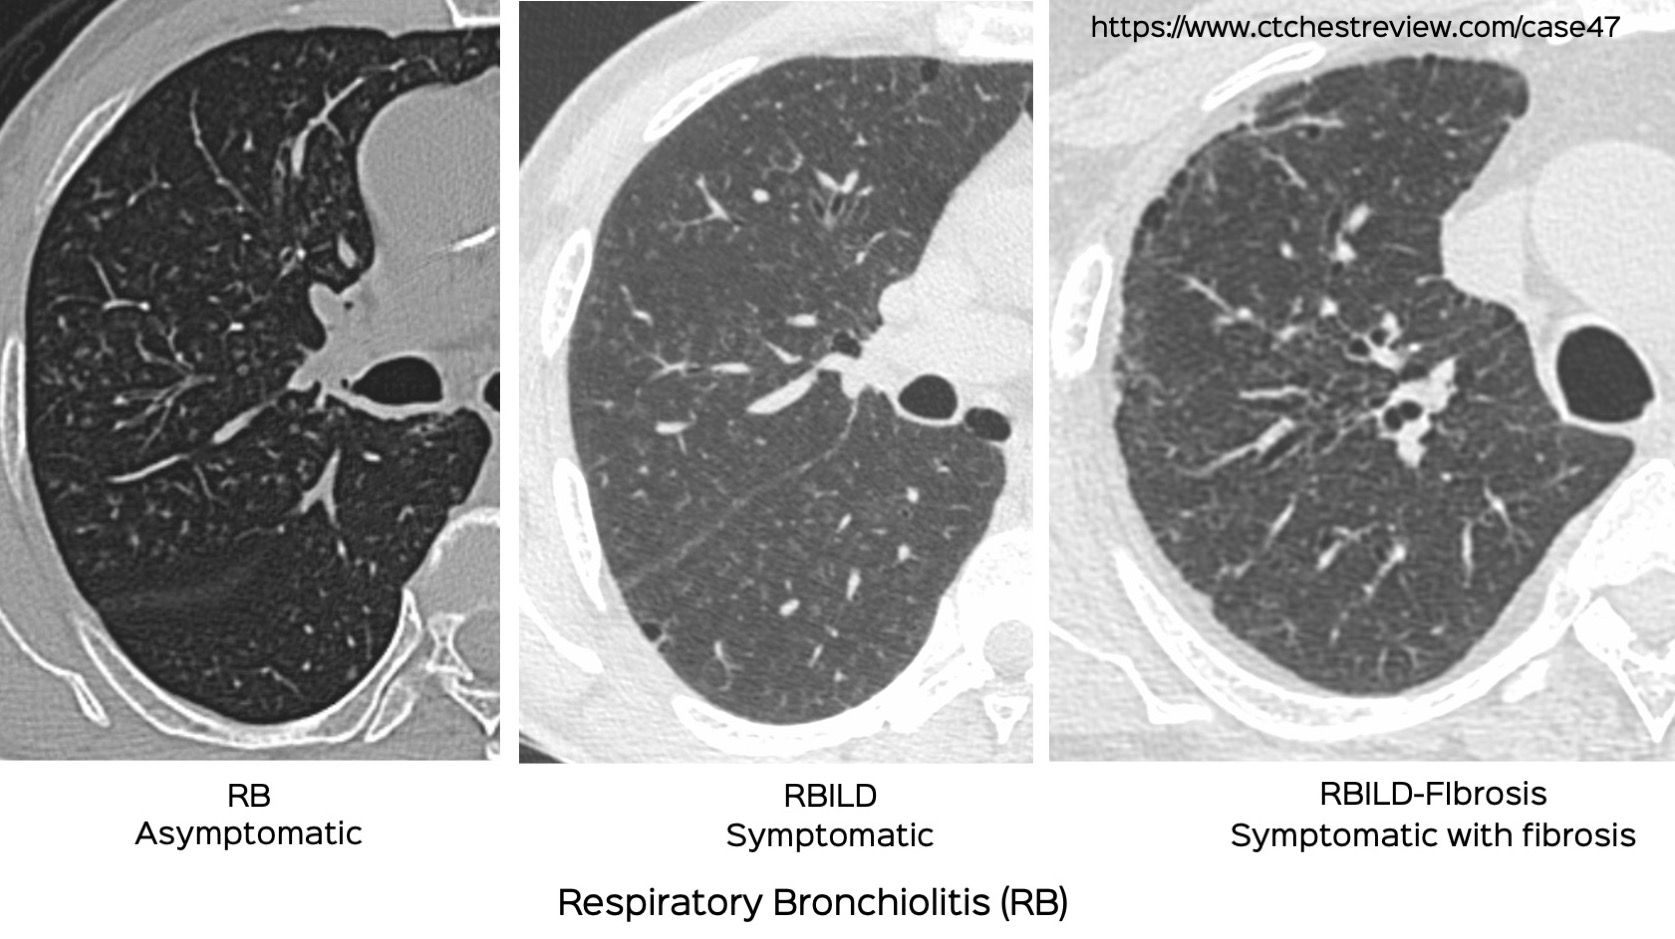

From www.ctchestreview.com

Case 47 When Does RB RBILD and RBILDFibrosis? Smoking Related Ild Radiology >95% of patients are actively smoking. There is strong evidence supporting a causal role for cigarette smoking in development of respiratory bronchiolitis ild (rb. At histological level, smoking causes a process of inflammation, destruction and subsequent lung remodelling, and is a risk. In this article, we describe and illustrate the characteristic clinical features, imaging findings, and pathologic findings of diffuse. Smoking Related Ild Radiology.